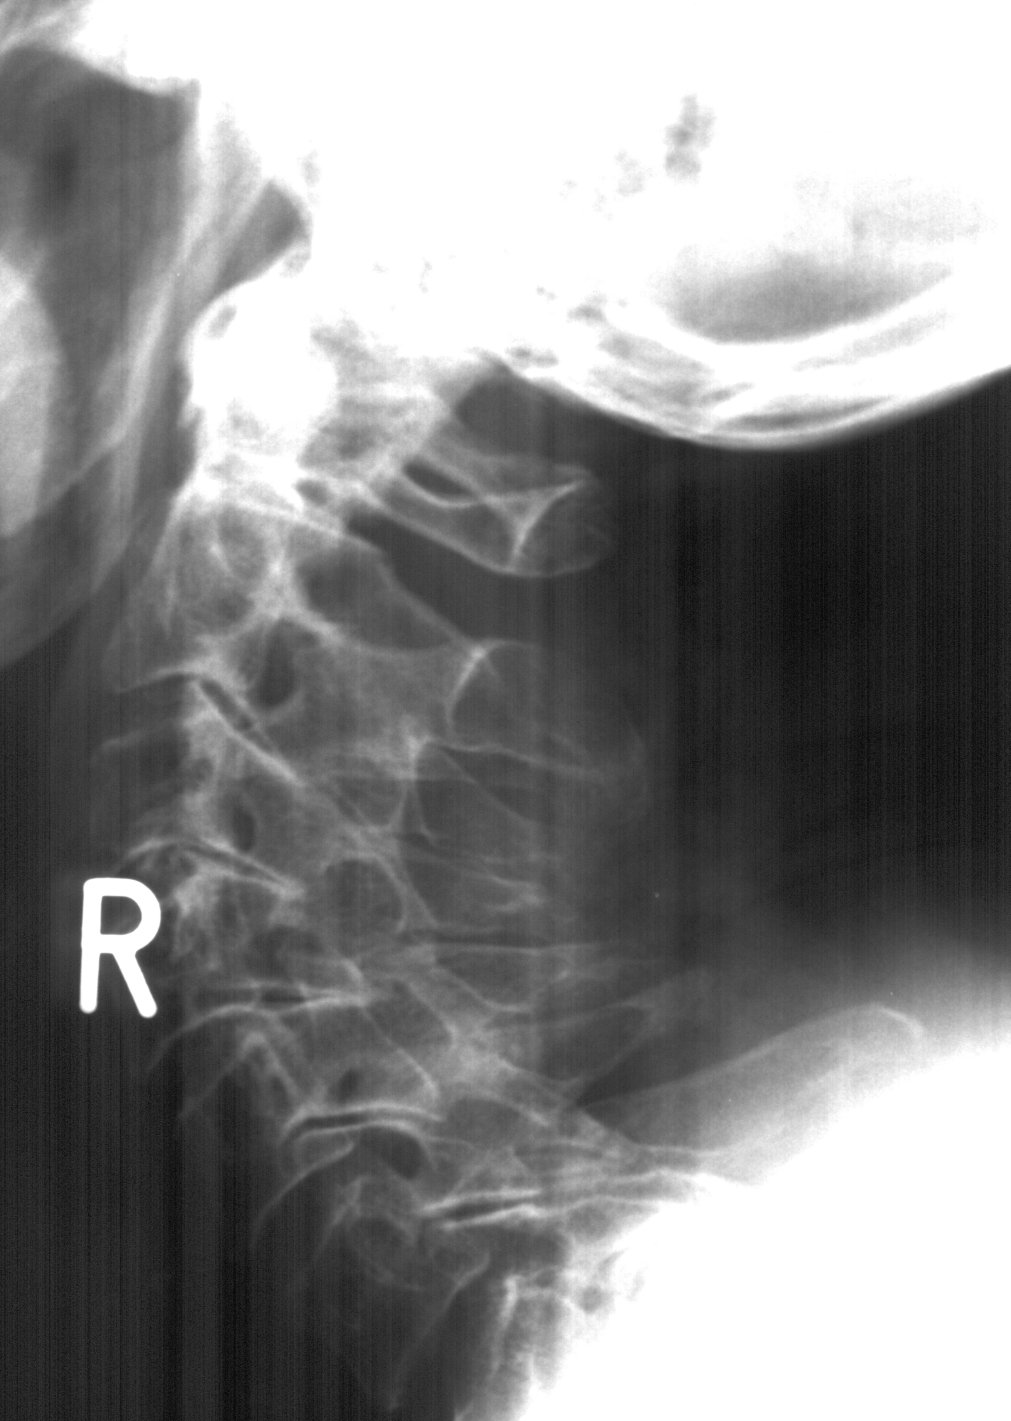

As I was almost over the constant pain in my right leg, a bicycle passed me without warning in the Rosestraße and I turned my head too energetically. That was in mid October> I am still having problems with this. The basic problem is my posture, see this in not the neck of a chicken but my very own neck.